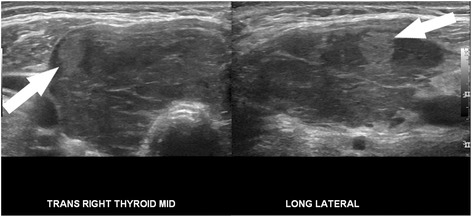

Ultrasound would be an ideal tool for prediction of indolent cancer, given that diagnosis of thyroid cancer almost always begins with sonographic evaluation of a thyroid nodule. An array of sonographic features has been used to describe thyroid nodules and identify those with features suspicious for malignancy. These features include microcalcifications, irregular borders, increased vascularity, taller-than-wide morphology, and marked hypoechogenicity (Fig. 1) [21, 22], though no single feature individually has proved to be very sensitive or specific. Conversely, a few sonographic patterns have been reliably associated with benignity in thyroid nodules, including a “spongiform” appearance (Fig. 2), an echogenic appearance in the setting of Hashimoto’s thyroiditis termed a “white knight” nodule (Fig. 3), a “giraffe skin” appearance, and a purely cystic nodule containing colloid without flow [23–25]. Elastography, a relatively new sonographic technique which assesses nodule stiffness, appears to correlate with malignancy, but further validation and wide-spread adoption will be required before stiffness measurements can be incorporated into routine thyroid nodule evaluation [26].

Fig. 3.

Very low suspicion pattern. Transverse and longitudinal sonographic images of the right lobe of the thyroid show an echogenic nodule (arrow) against a background of hypoechoic, enlarged thyroid with curvilinear echogenic bands. These features of the background thyroid are characteristic of Hashimoto’s thyroiditis. The echogenic nodule is a benign “white knight” nodule, representing a regenerative nodule